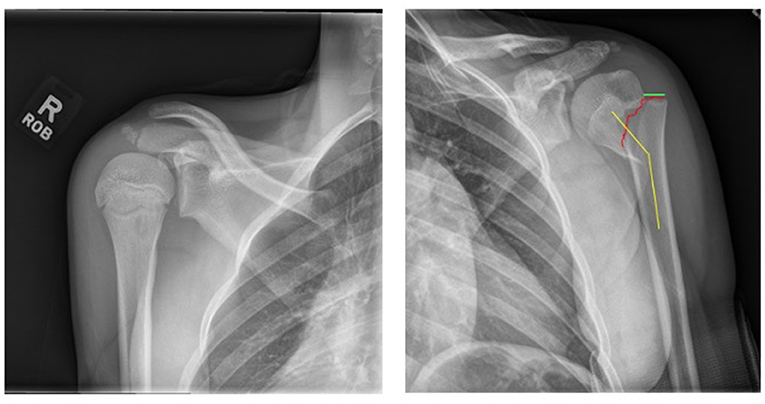

An X-ray of the broken arm can tell doctors if the humerus has moved out of place, which is called displacement, or if it is left at an angle instead of being straight, which is called angulation (Figure 1). Our study specifically looked at serious fractures that were displaced more than half the width of the bone and angled more than 30 degrees.

- Figure 1 - X-ray showing a non-injured shoulder on the left and a proximal humerus fracture (red line) on the right, with displacement (green) and angulation (yellow).